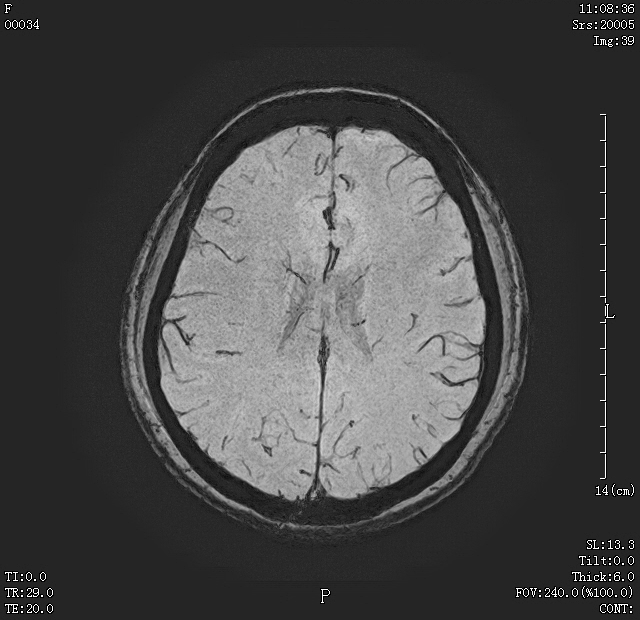

07 颅脑磁敏感加权成像(SWI) 可发现颅内微小出血灶;静脉畸形等;可发现高血压及外伤后患者的微小出血灶。